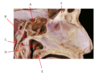

Which nerve is labeled by C?

Inferior alveolar

(Branch of CN V3)

A.

B. Chorda Tympani (branch of CN 7)

C. Inferior Alveolar n. (branch of CN 5.3)

D. Facial n. (CN 7)

E. Lingual n. (branch of CN 5.3)

F. Posterior Superior Alveolar n. (branch of CN 5.2)

G.

H.

I. Mental n.